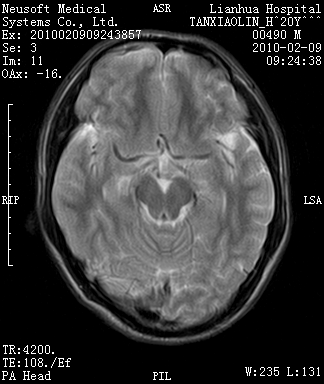

20岁男性患者,平时偶有头痛而无其他不适,现因持续头痛服药后无缓解而来院就诊。

松果体囊肿?

松果体区占位继发轻度脑积水?该患者有ct资料,我已发上。

考虑松果体囊肿。